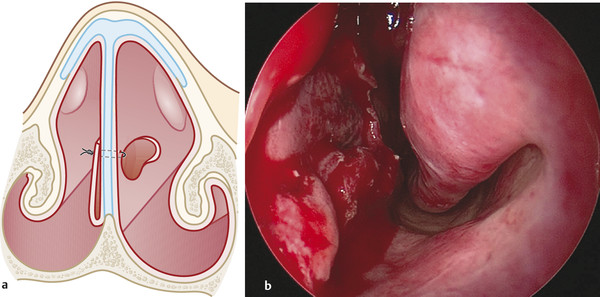

Suturing of the flap. Sutures (synthetic absorbable polyglycolic acid suture; 4–0) should be placed in the superior border of the flap (anteriorly and posteriorly) avoiding tension of the tissue (Fig. 17‑6).

Verify the total coverage of the septal perforation from the other nasal cavity (Fig. 17‑7).